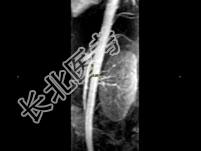

- 多项选择题女,24岁, 发作性肉眼血尿1年,实验室检查: 尿蛋白(-~+)、红细胞(1~2/HP),尿蛋白直立试验(+), CT扫描如图,下列说法正确的是 ( )

B、左肾静脉走行至肠系膜上动脉与腹主动脉间变细,近左肾处扩张

E、考虑为左肾静脉胡桃夹综合征